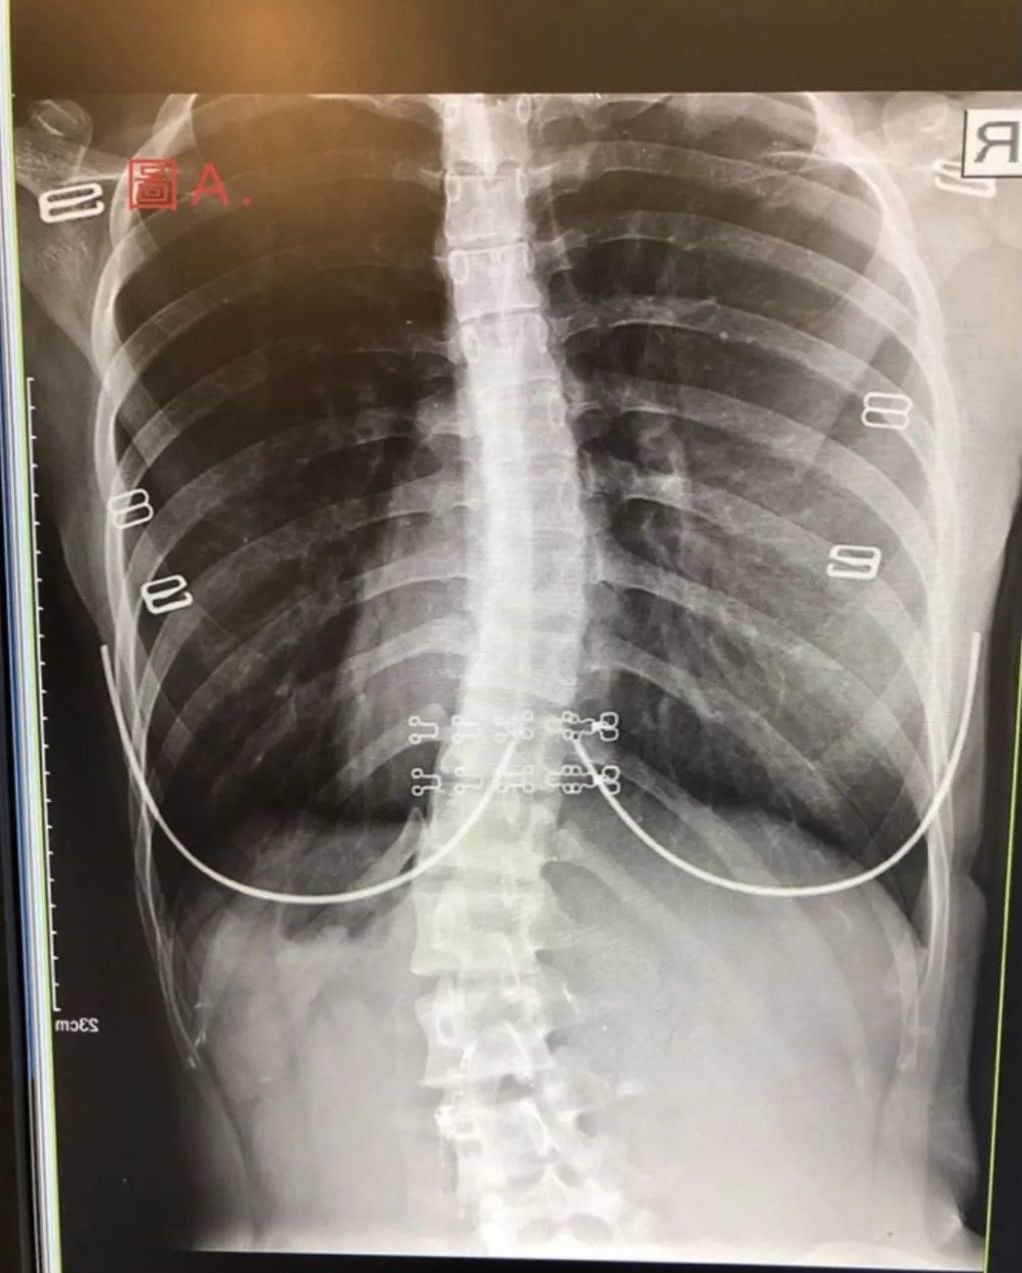

这类型脊柱侧弯大多数因为脊柱受伤过,导致肌肉紧绷、或是骨盆歪斜、以及长短脚等因素使得身体因为疼痛姿势而引起的弯曲。此类的脊柱侧弯,脊柱本身没有任何的问题。因此只要有效的针对弯曲的角度做治疗或调整,便能有效的改善弯曲度数。我们可以通过运动以及姿势训练及关节矫正等非侵略性,较温和的方式来治疗改善。

由X光片可以看出功能性的脊柱侧弯在站姿下(左图),因为脊柱需要对抗重力,因此会因为脊柱两侧肌肉不正确出力而产生曲度,但在非抗重力的躺下(右图)脊柱就又会呈现直立的正确姿势了。此类的脊柱侧弯患者脊柱本身并没有问题,只需要学习如何控制肌肉的力量便可改善。